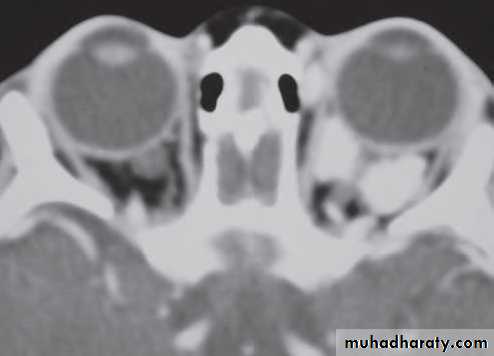

• Investigation: MRI is the investigation of choice, CT shows thickening and calcification of the optic nerve.

• Investigation: MRI effectively demonstrates the tumour, and may show intracranial extension if present.